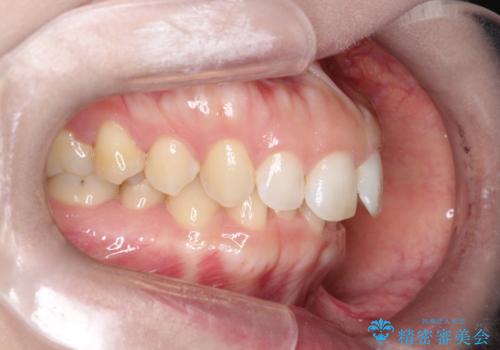

- 前歯の凸凹を主訴に来院されました。

深い噛み合わせも同時に治療を行う計画を立て、インビザラインを使用して歯並びの改善を行うことができました。

叢生改善のために遠心移動とIPRを行なっています。